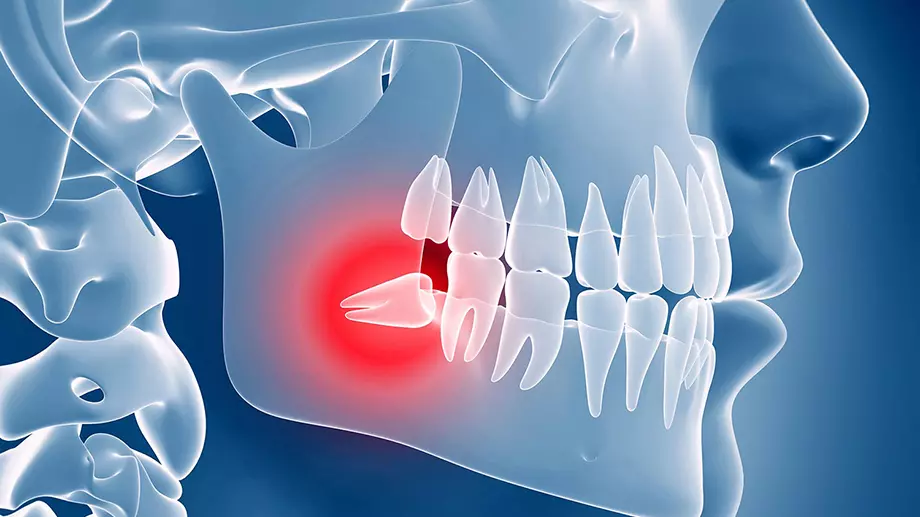

درد و ناراحتی ناشی از دندانهای نهفته شما را آزار میدهد؟

دندانهای نهفته، دردسرهایی جدی برای سلامت دهان و دندان به همراه دارند. ممکن است شما هم از دردهای شدید دندانها، احساس فشار و یا حتی عفونتهای مکرر رنج ببرید. اگر همچنان از جراحی دندان نهفته هراس دارید، بدانید که این فقط یک گام ساده است تا به راحتی از درد و مشکلات دندانی رها شوید.

چگونه تشخیص دهید که دندان شما نیاز به جراحی دارد؟

دندانهای نهفته معمولاً به دلیل عدم رویش کامل در فک یا فضاهای محدود در دهان، در زیر لثه گیر میکنند. علائمی مانند درد مزمن، التهاب لثه، ایجاد کیست یا عفونت، و یا فشار به دندانهای مجاور از جمله علائم دندان نهفته هستند.

چرا جراحی دندان نهفته باید انجام شود؟

دندانهای نهفته میتوانند باعث مشکلات متعددی مانند:

عفونتهای مکرر

درد شدید

ایجاد آسیب به دندانهای مجاور

به هم ریختگی ساختار دهان و فک